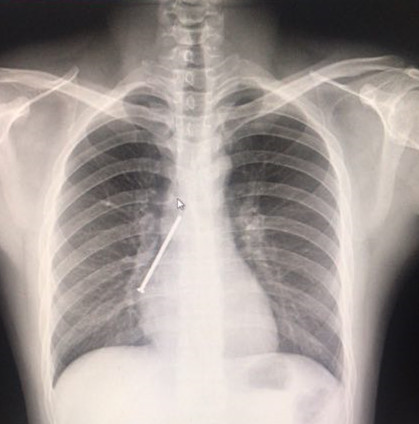

两周前,王明在和朋友打赌时不慎将一枚生锈的铁钉吞下,随后出现了剧烈的干咳、胸痛、气促。在当地多家医院就诊,都无法取出,很多医生都建议手术开胸取钉。直至6月28日下午王明在姐姐的陪同下来到南方医院呼吸与危重症医学科就诊,接诊的佟万成主任医师看到王明的胸片后意识到情况非常危险,立马安排患者迅速完成必要的术前检查,并联系呼吸内镜中心为患者开通绿色通道。

经过该科室蔡绍曦主任、佟万成主任医师、刘来昱主任医师的研究,发现患者右下肺异常高密度铁钉样阴影,较前并没有明显的变化,担心铁钉已经扎透气管壁,于是讨论制定了三套治疗预案,如有意外随时做好急诊开胸手术的准备。经过一系列准备后,刘来昱主任医师为王明实施了经气管镜异物取出术。

患者胸片中铁钉样阴影清晰可见